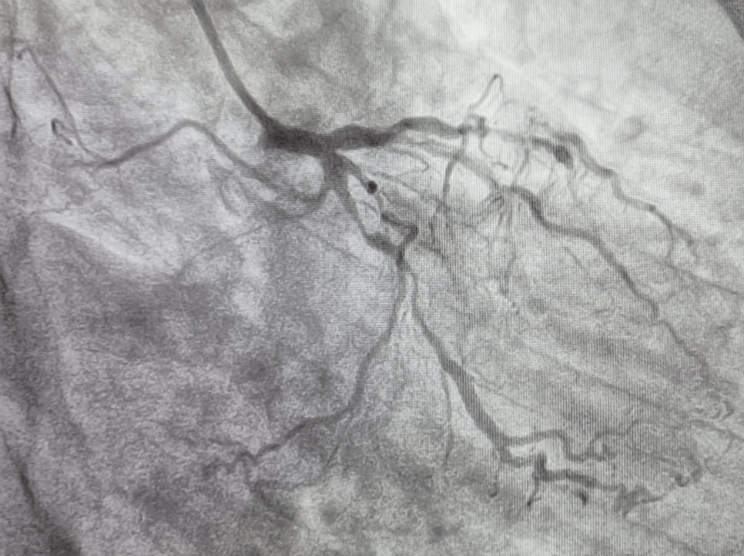

Findings of CAG

• Patient has extensive triple vessel disease with total occlusion of mid LAD. LCX diffuse 90% & RCA diffuse 90% stenosis & distal RCA total occlusion.